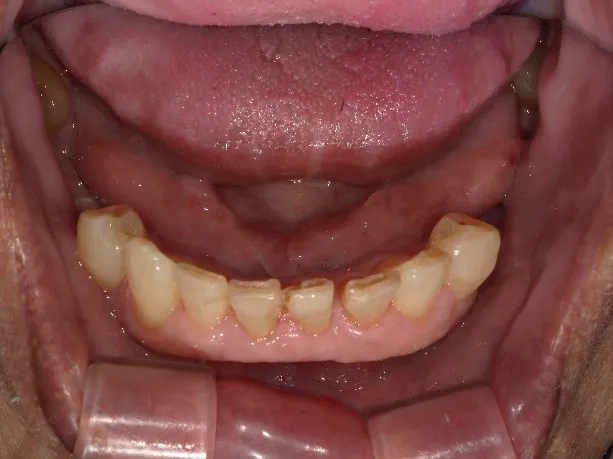

症例1 バネの見えないスマイルデンチャーで咬合を回復した症例

| 患者様 | 70代 男性 |

| 治療箇所 | 右下76 左下67 ノンクラスプデンチャー(スマイルデンチャー) |

| 治療費用 | 275000円 |

| 治療期間 | 4ヶ月 |

| 通院回数 | 12回 |

| 副作用やリスク | 慣れるまで違和感があることがあります。使用状況によっては保定装置が緩んだり掛けたりする可能性があります。 |

こちらの方は、前院長の時代から長くこみね歯科医院をご愛顧頂いている方です。長く定期的なメンテナンスも通って頂き、口腔ケアにも熱心に取り組んで頂いています。

今回はどうしても残すことができない状態の奥歯を抜歯し、そこへ部分義歯(スマイルデンチャー)を製作することになりました。

奥歯の欠損の治療方法としては大きく3つが考えられます。

一つ目はブリッジの治療ですが、一番奥の歯でしたので、欠損した歯の両端に橋渡しすることができず不採用となりました。(一番の奥の親知らずはありますが、支台となる歯としては適していないため)二つ目はインプラント治療です。チタン製の人工歯根を外科的に歯ぐきの中に埋め込み、その軸の上に人工歯をかぶせる方法です。

レントゲン、CT撮影などの精密検査の結果、奥歯の咬合力を支える骨の状態を精査し、外科的な侵襲や、治療期間、経済性なども考慮し、今回は採用しませんでした。三つ目が部分義歯です。保険治療の制限の中ではできない、ノンクラスプデンチャー(金属のフックが見えないタイプ)を選択されました。

形状の設計においては、しっかり咬合する役割の奥歯の左右両方ですので、本来は両側にまたがる一体型の義歯で安定させたいところです。そうなると見えない部分とは言え、下の前歯の裏側を入れ歯の床(ピンク色のプラスティック部分)で覆うことで多少の違和感は否めません。

できるだけ違和感の少ないように、大きな入れ歯は避けたいというご要望もありましたので、今回は左右別々の小さい入れ歯を2つ製作することとしました。

小さいスマイルデンチャーは、特殊なナイロン製の樹脂がとてもしなやかで割れにくいので、落としたり誤って踏んでしまっても壊れにくい素材でできています。また、非常に薄く、軽いのが特徴です。これまで全国で25万症例を超えており、ノンクラスプデンチャーの中でも非常に信頼性の高いものです。

現在も月1回ペースで、メンテナンスにお越しなり、チェックと専門のクリーニングを欠かさず受けておられます。こみね歯科では、「患者様参加型治療」を目指しています。

そのために、検査の段階からできる限り手鏡、写真、マイクロスコープ、検査結果などで口腔内を可視化し、多くの治療選択肢の中から一緒に治療方法を選んで頂いていますので、安心してお気軽にご相談ください。